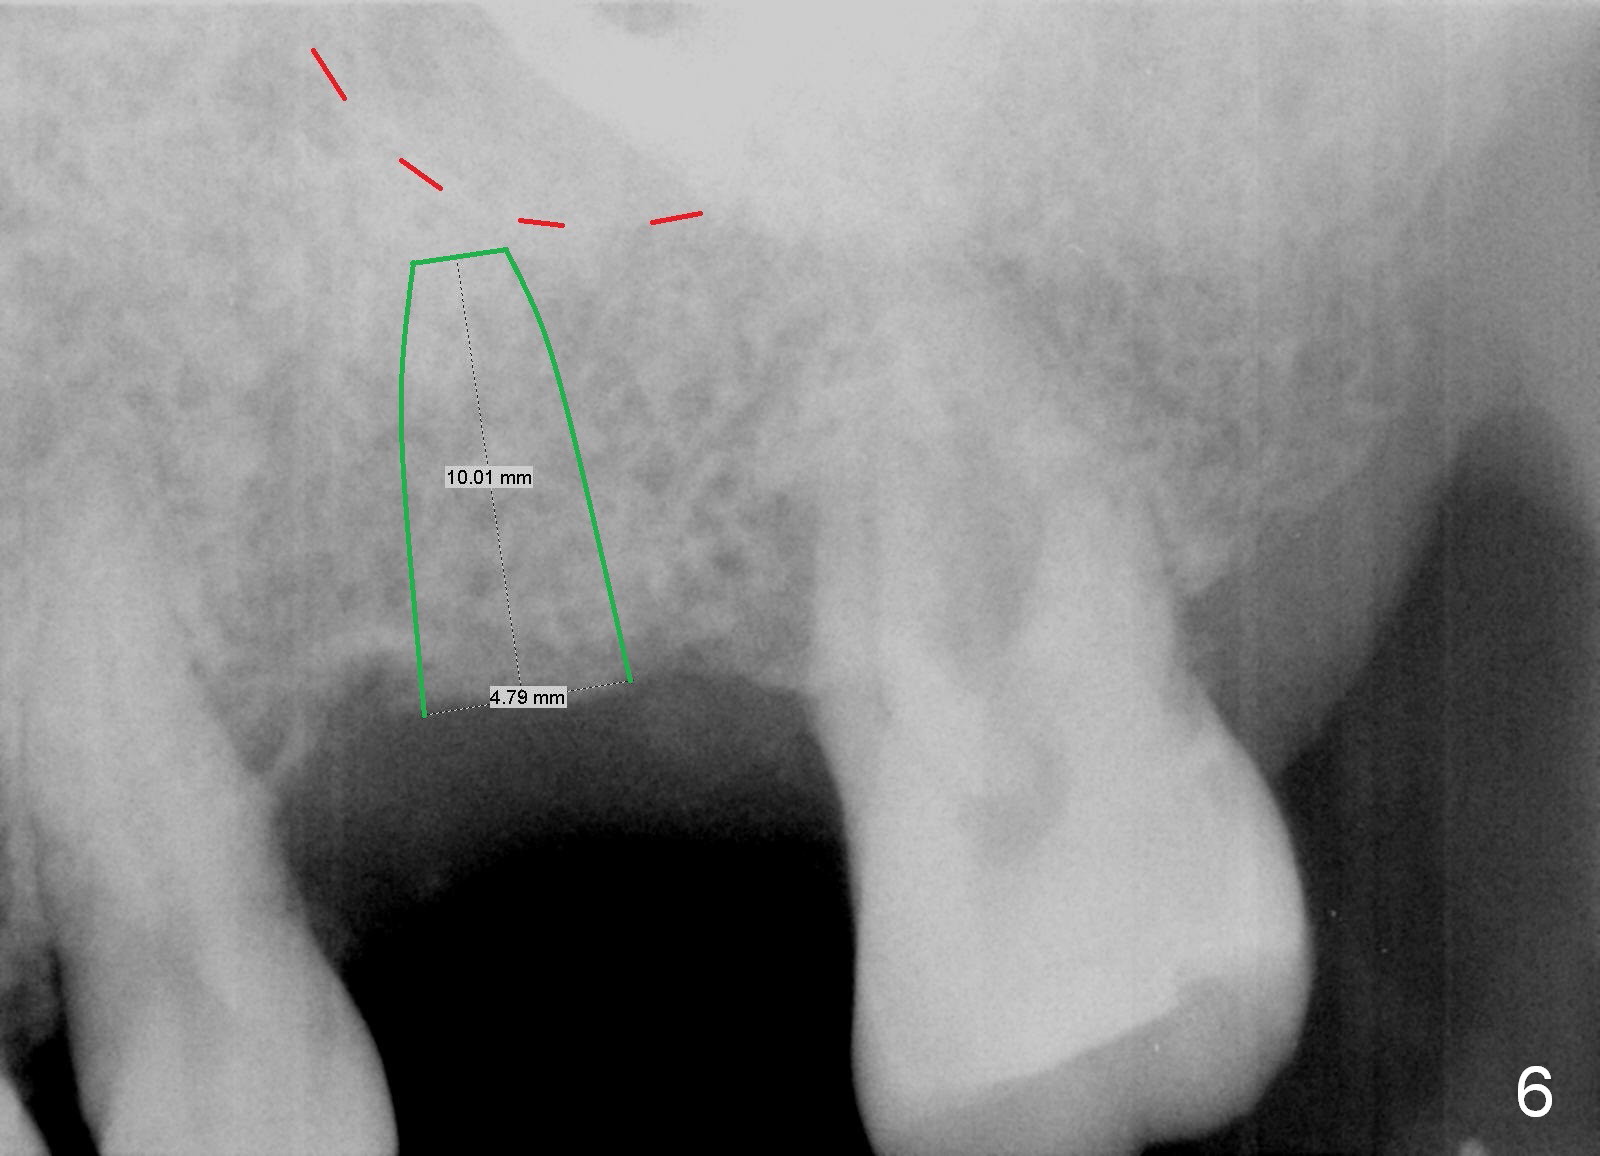

Re-analysis of #14 edentulous area reveals slightly unfavorable crown/implant ratio if the implant reaches the 1st line of the sinus floor (Fig.4). A 5x13 mm implant may invade the 1st line (Fig.5). Therefore the depth of osteotomy using 4.8 mm Magic Drill is 9-10 mm (Fig.6 green), followed by Magic Sinus Lifter, unless the bone density is high.